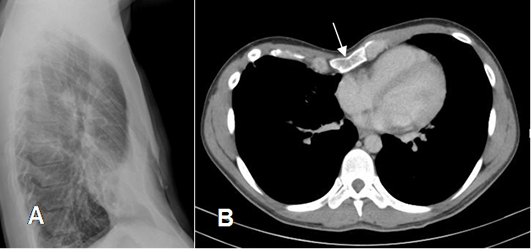

Fig 18. Pectum excavatum.

A: RX lateral. No se encuentran alteraciones significativas en el esternón.

B: TAC axial. Desplazamiento posterior del esternón que comprime la silueta cardiaca y la desplaza hacia la izquierda, por pectum excavatum.